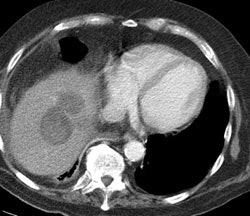

Hepatocellular carcinoma: The patient shown below had a large hepatocellular carcinoma (black arrows). Small satellite lesions were seen in other segments of the liver (white arrow). The FDG PET exam demonstrated only mildly increased uptake of tracer within the patients large primary lesion and the smaller satelite lesions could not be identified. |

|